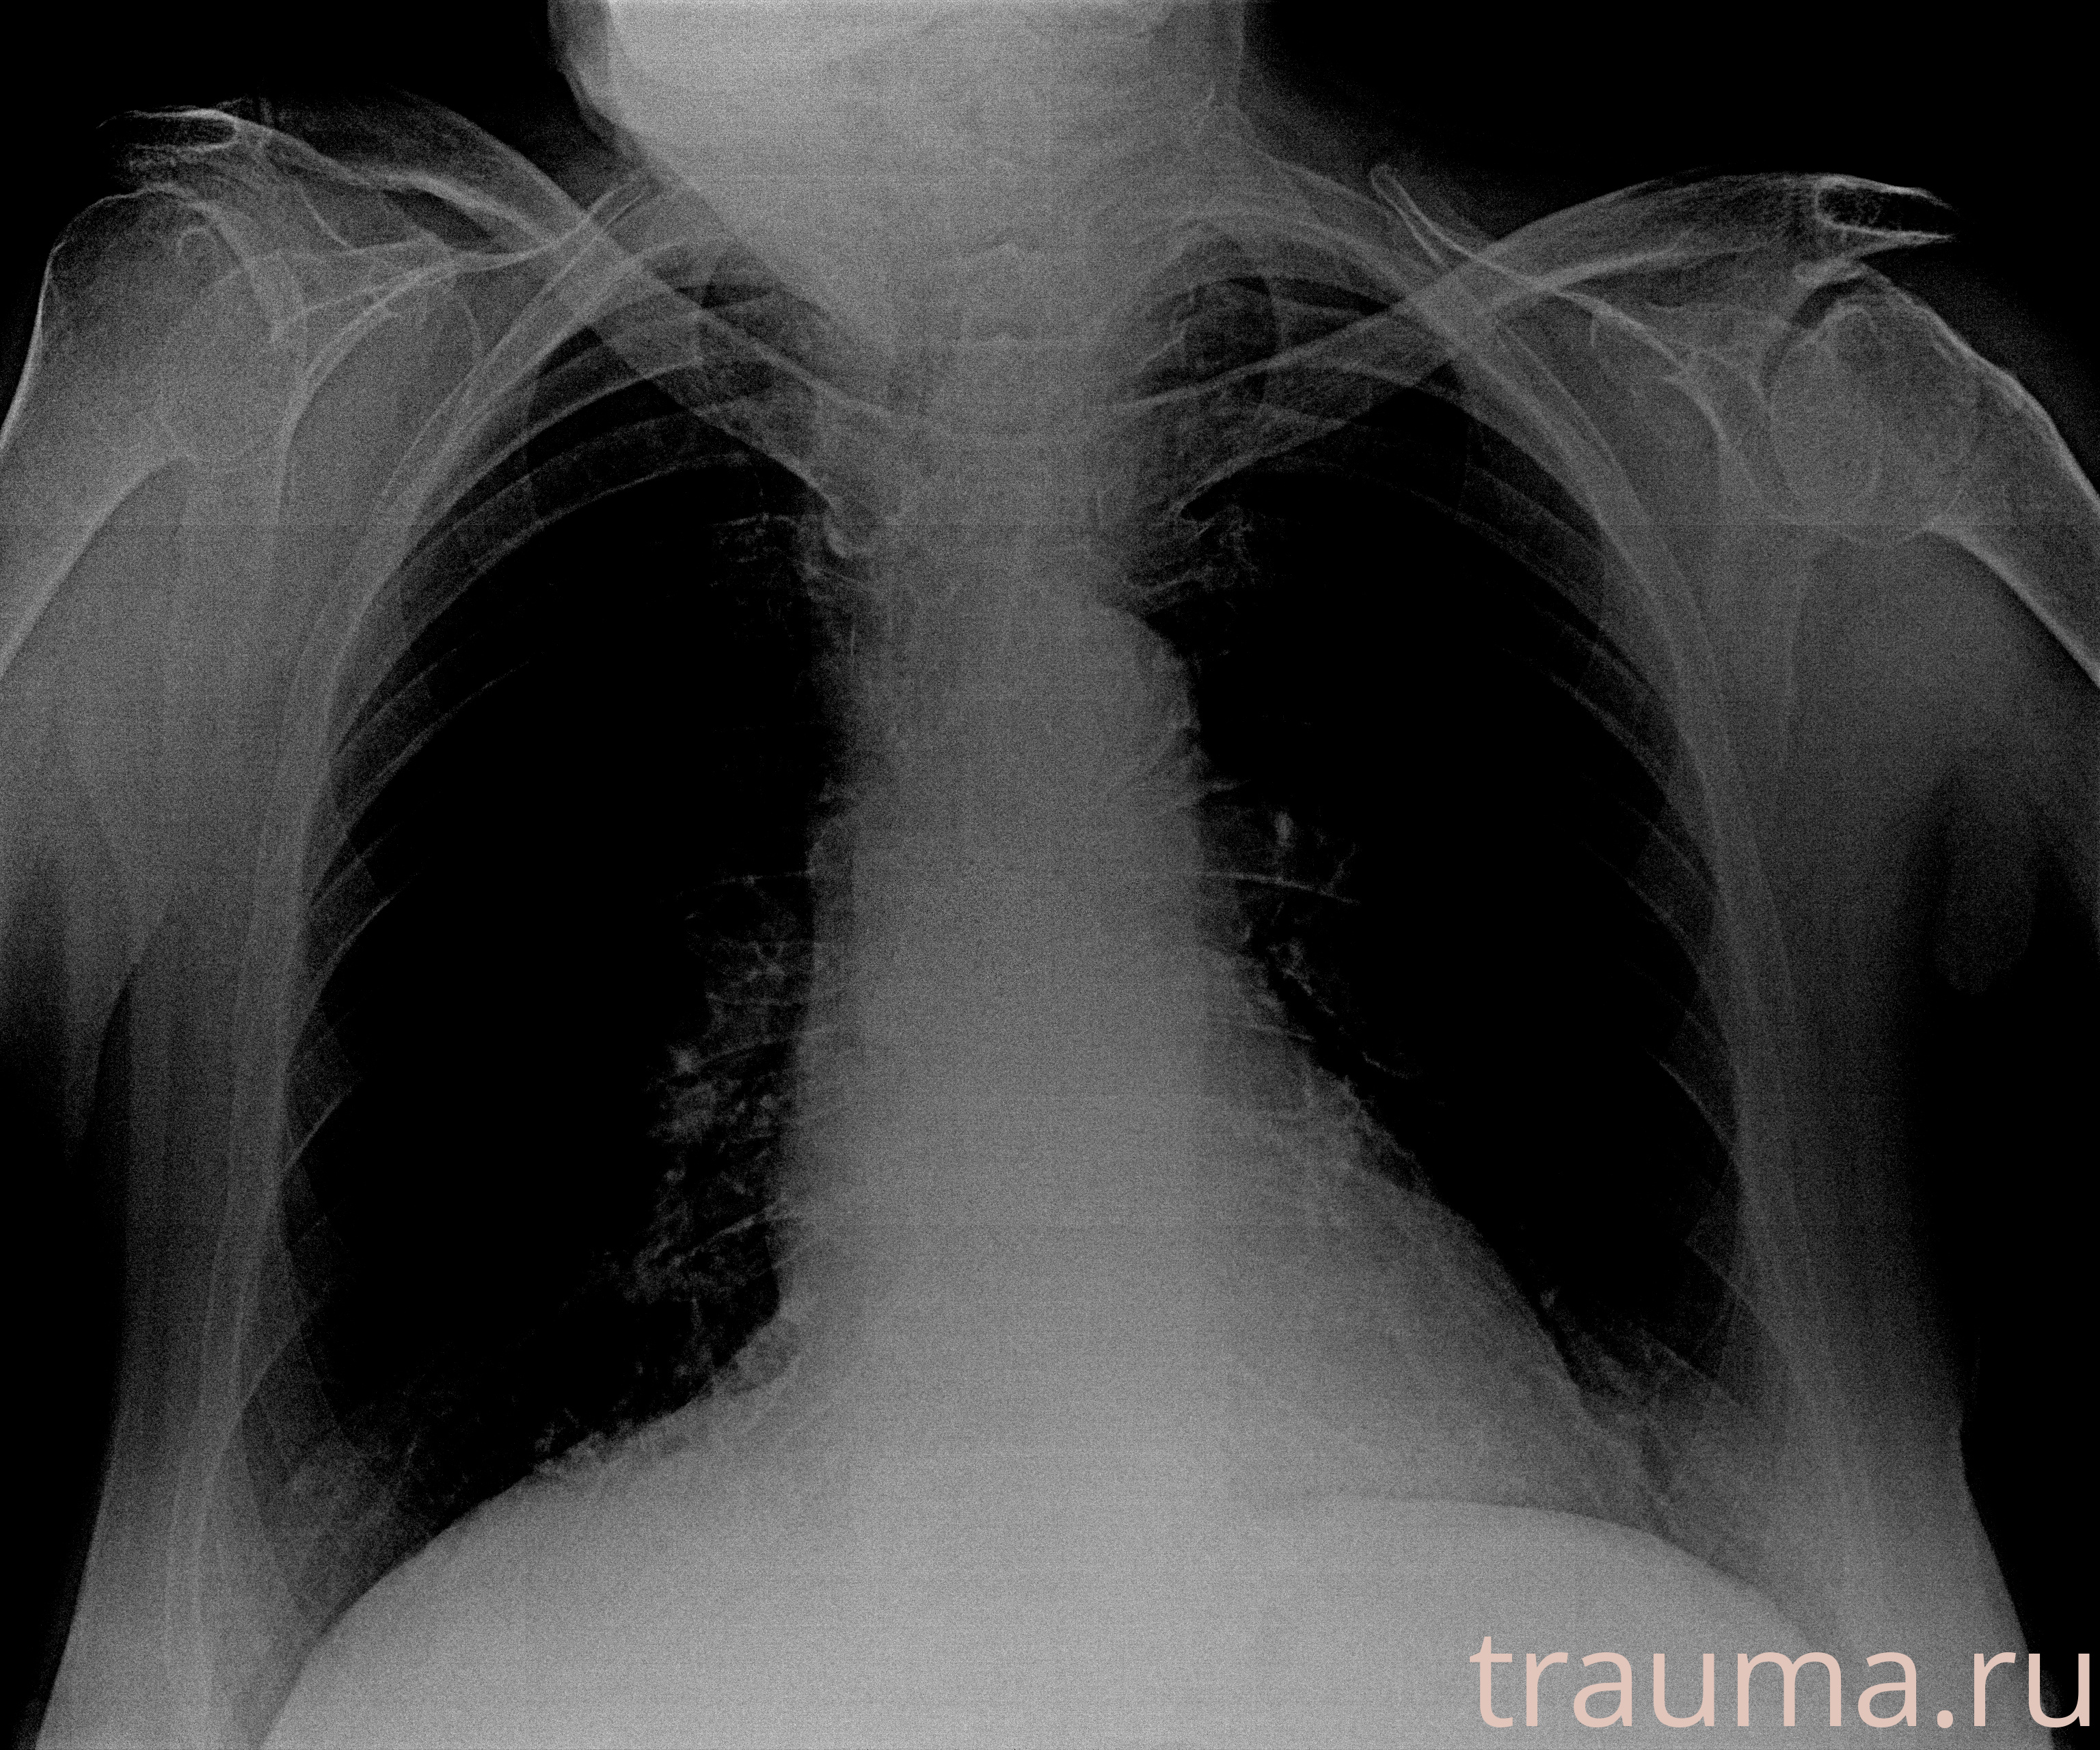

Рентген на дому: по вашему адресу приезжает врач-рентгенолог, травматолог-ортопед с мобильным рентгеновским аппаратом, проводит диагностику травмы или заболевания, делает необходимые рентгенограммы, дает рекомендации по дальнейшему лечению. Получить качественные снимки в домашних условиях возможно благодаря уникальной методике, разработанной МосРентген Центром для института  Склифосовского

при переломе шейки бедра и пневмонии от компании МосРентген Центр - партнера Института имени Склифосовского